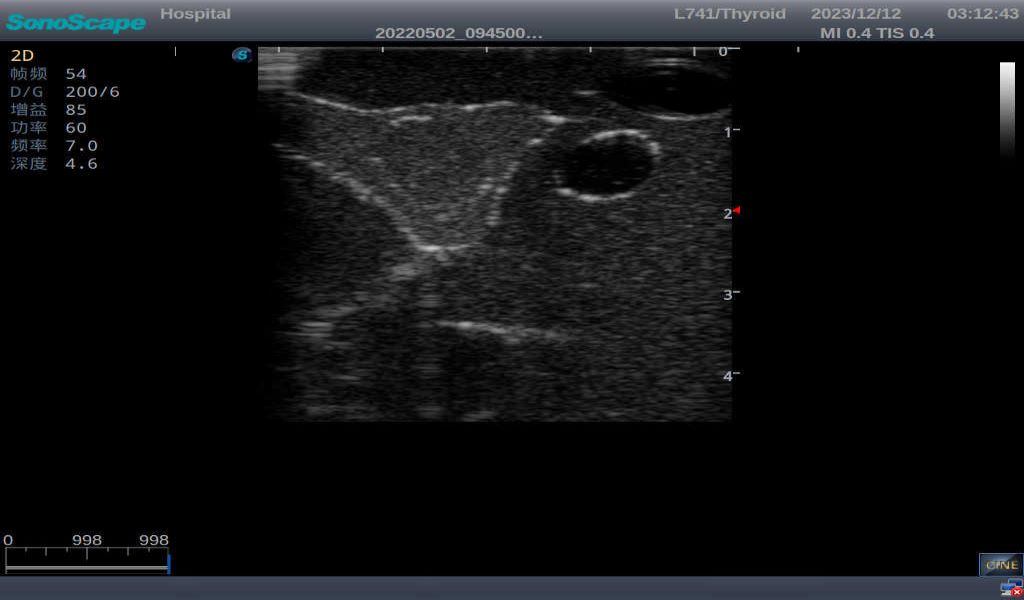

3)       It comes with four (4) thyroid modules and can show five (5) ultrasonic images: normal thyroid, thyroid adenoma, thyroid cancer, nodular goiter, thyroid cyst

Normal thyroid with homogeneous parenchymal echo and well-defined capsule